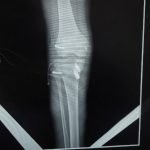

Orthopaedic Surgeon | Arthroscopy & Joint Replacement Specialist

Dr. Aditya Tripathi is a dedicated and skilled Orthopaedic Surgeon specializing in sports injuries, arthroscopy, and joint care. Known for his clinical precision, ethical practice, and patient-first approach, he focuses on helping patients regain mobility, strength, and confidence through evidence-based orthopaedic treatment. His academic background and hands-on clinical training reflect a strong foundation and a commitment to excellence in orthopaedic care.

Dr. Aditya Tripathi is widely appreciated by patients for his clear communication, honest medical guidance, and personalized treatment approach. His expertise in managing ACL tears, ligament injuries, shoulder conditions, and sports-related injuries makes him a trusted choice for comprehensive orthopaedic and sports injury care. Patients value his attention to detail, compassionate care, and focus on long-term recovery—establishing him as a reliable and respected orthopaedic specialist.

- Robotic Joint Replacement

- Knee Replacement Surgery

- Hip Replacement Surgery